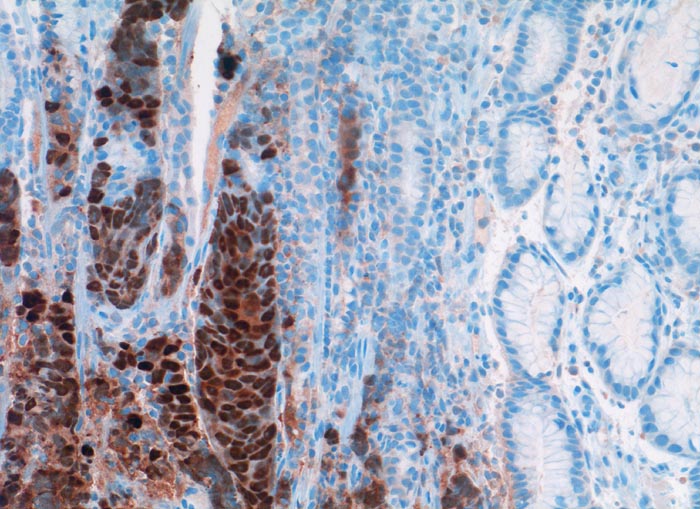

Metastase: invasiv duktales Mammakarzinom

Magenantrum

Die Tumorzellen füllen die Drüsenschläuche des Magens aus und verdrängen die orstständigen Zellen. Die Tumorzellkerne sind stark positiv für den Östrogenrezeptor.

Seit 21 Monaten bekannte Metastasen eines invasiv duktalen Mammakarzinoms im Magenantrum

Histologie

Immunhistochemie

Oestrogen Rezeptor

200